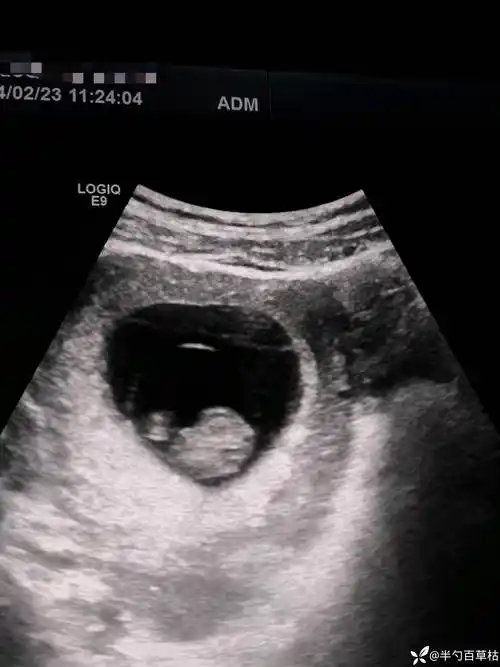

桃心78形状的孕囊关于绒毛膜囊羊膜囊卵黄囊